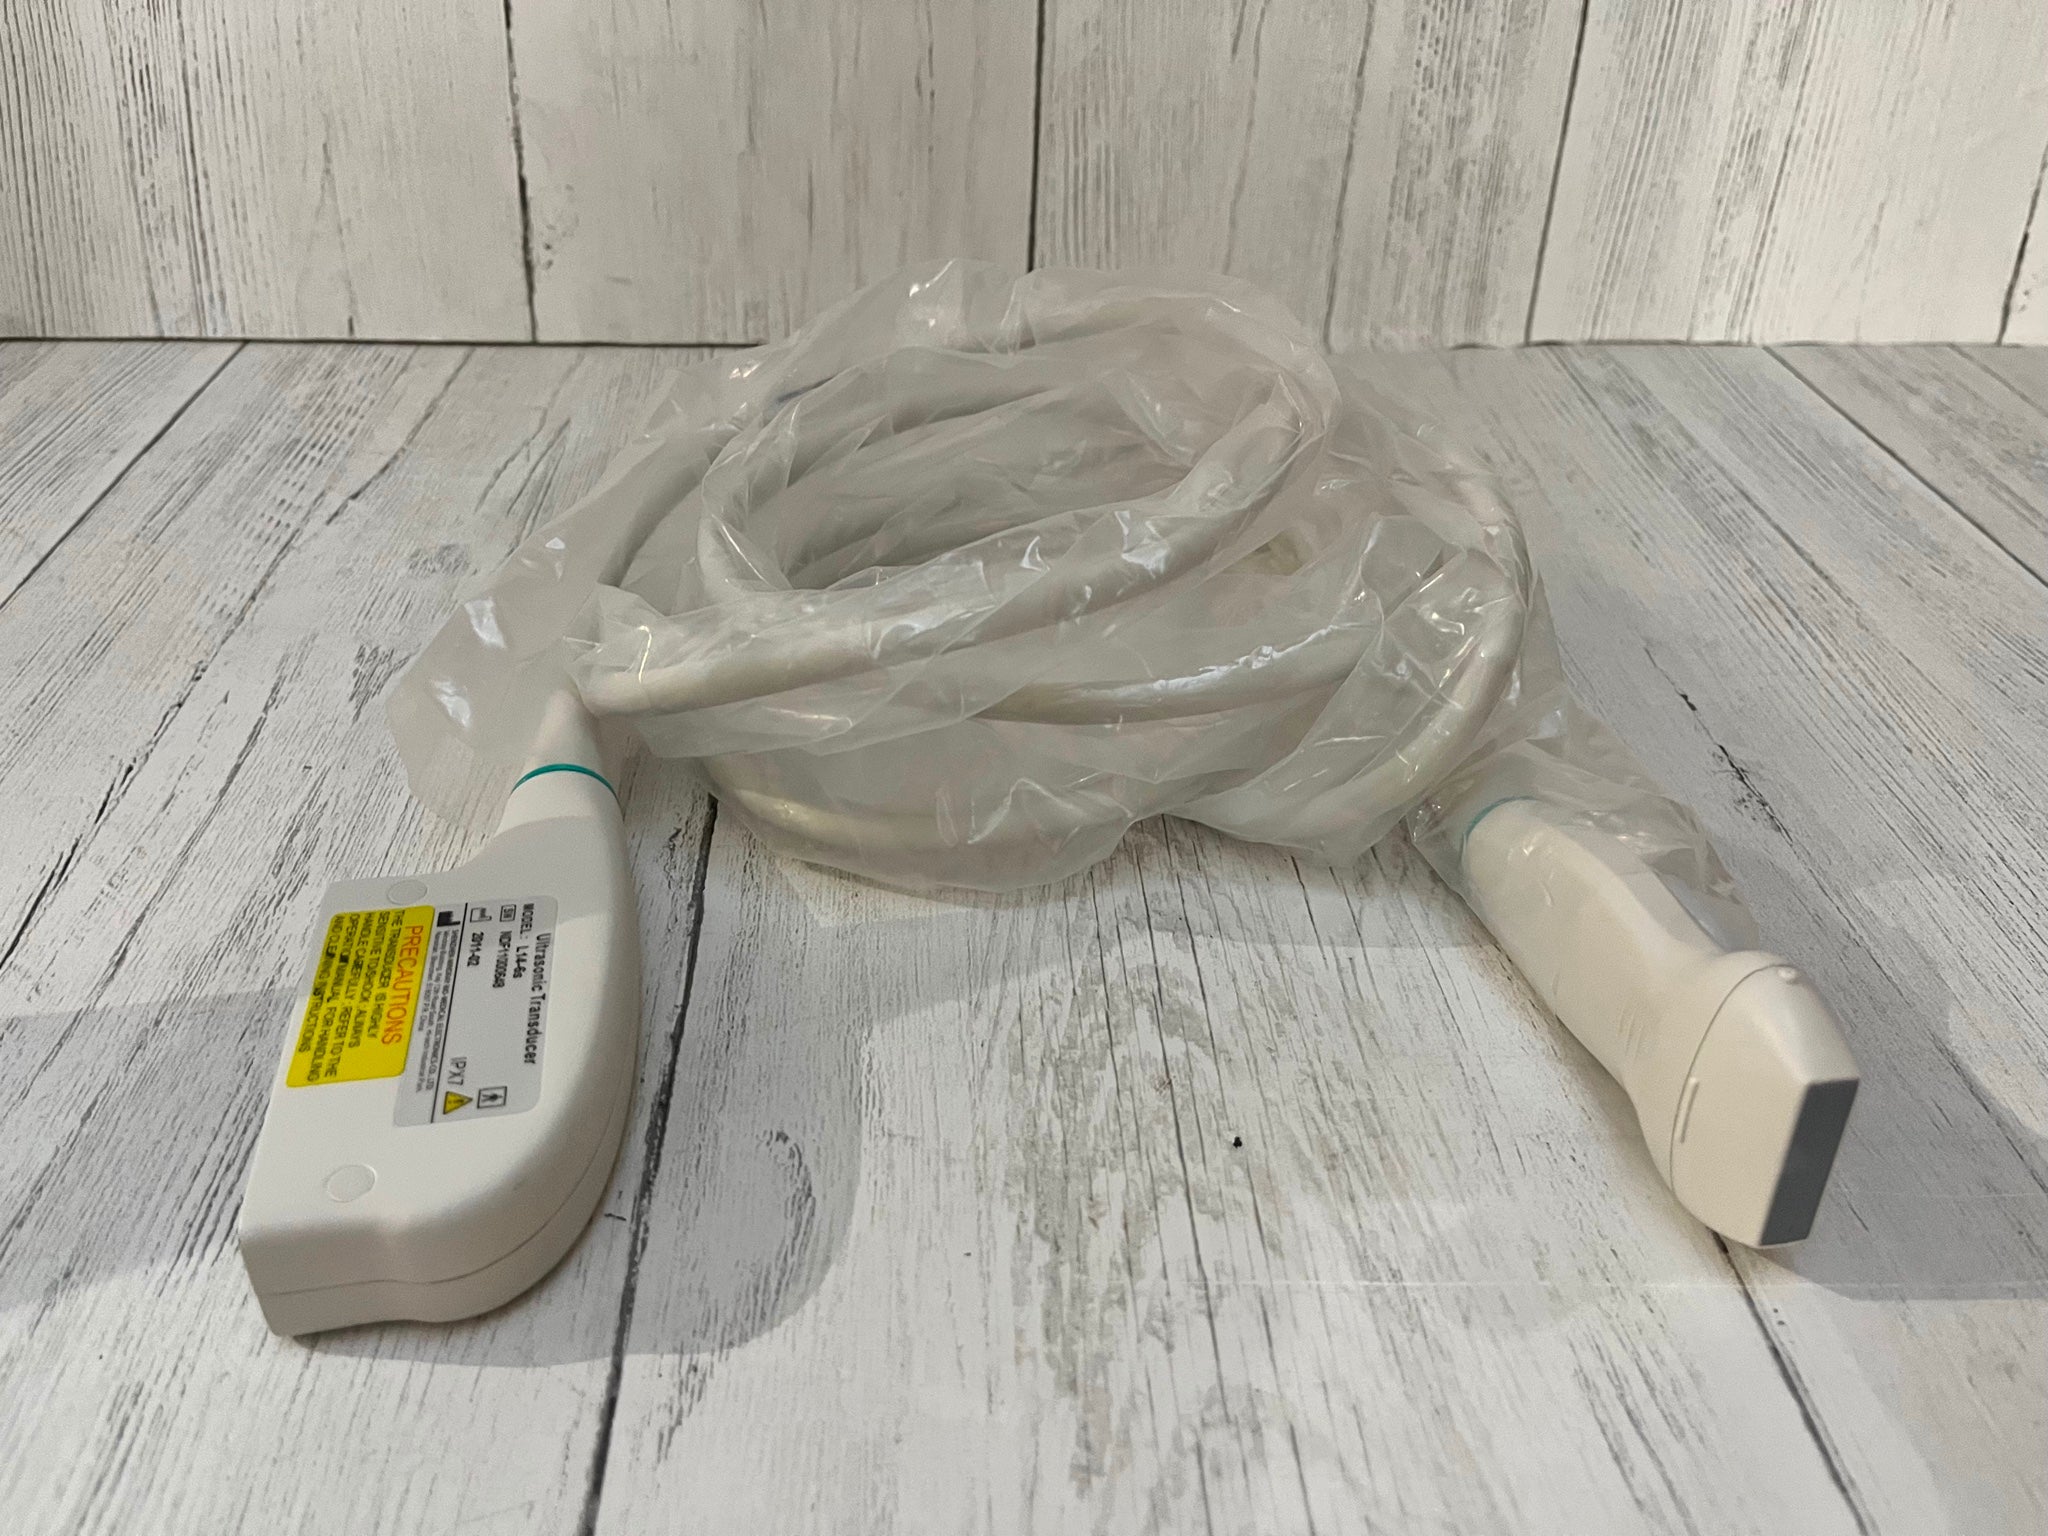

Description

ATL HDI 3500 w/ 2 Probes